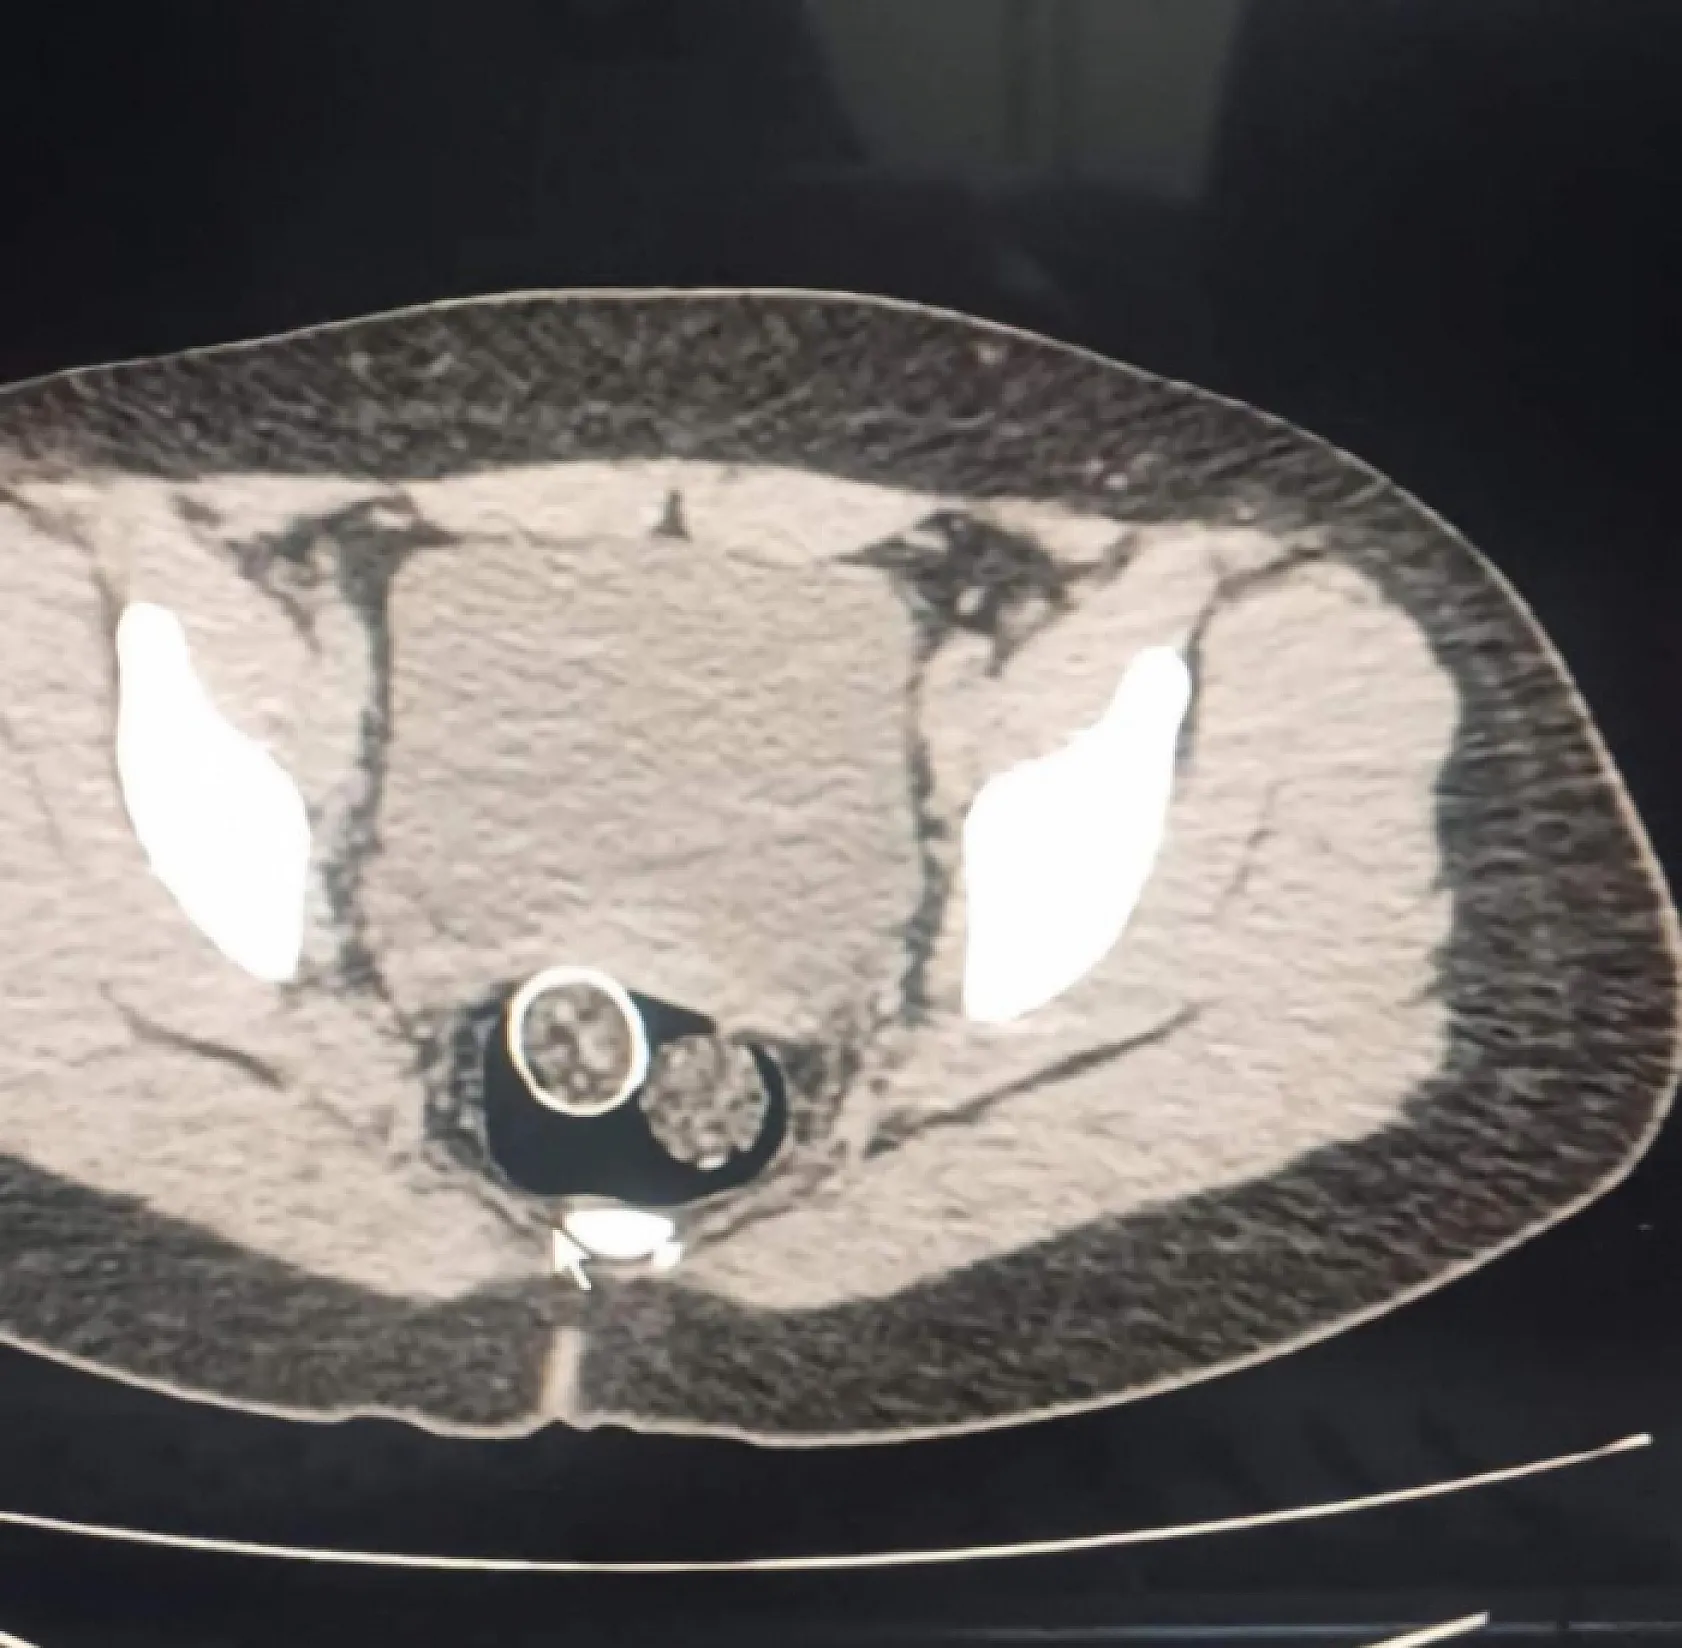

320 gram uyuşturucuyu mide ve rahme sakladılar

Polisin düzenlediği uyuşturucu operasyonunda gözaltına alınan 5 şüpheliden 2'sinin yapılan iç beden muayenesinde rahim ve mideye saklanmış 320 gram uyuşturucu madde ele geçirildi.